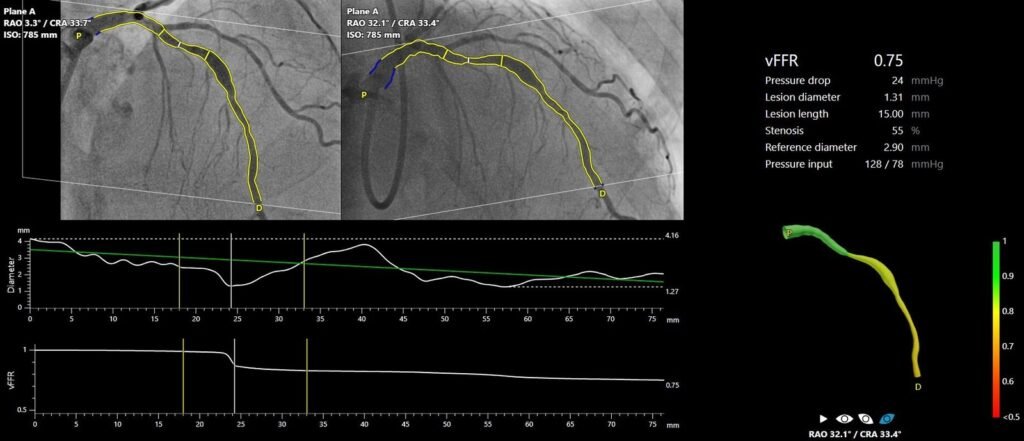

FAST III war eine vom Prüfarzt initiierte, offene, multizentrische, randomisierte Studie, in der eine vFFR-geführte mit einer FFR-geführten Koronarrevaskularisation bei 2235 Patienten mit intermediären Koronarläsionen (definiert als 30-80%ige Stenose durch visuelle Beurteilung oder QCA) verglichen wurde. Intermediäre Läsionen wurden physiologisch anhand von vFFR oder FFR auf der Tischseite beurteilt und behandelt, wenn vFFR oder FFR ≤0,80 waren. Der primäre Endpunkt war ein Kompositum aus allen Todesursachen, einem Myokardinfarkt oder einer Revaskularisierung 1 Jahr nach der Randomisierung.

„Die Ergebnisse von FAST III bestätigen die Sicherheit und Machbarkeit des Online-Einsatzes der vFFR als einfaches, minimal-invasives Instrument zur Anleitung der Revaskularisation bei Patienten mit intermediären Koronararterienläsionen, die eine physiologische Beurteilung der Läsion benötigen. Die Technologie hat das Potenzial, den Einsatz der Physiologie zu verstärken, was die Prognose von Patienten verbessern könnte, bei denen die Entscheidung zur Revaskularisierung intermediärer Koronararterienläsionen immer noch weitgehend auf Augenmaß beruht. Der Einsatz der vFFR macht Führungskatheter, invasive Koronararterieninstrumente und hyperämische Wirkstoffe überflüssig, die mit Risiken und Unannehmlichkeiten für den Patienten verbunden sind„, so Dr. Joost Daemen.